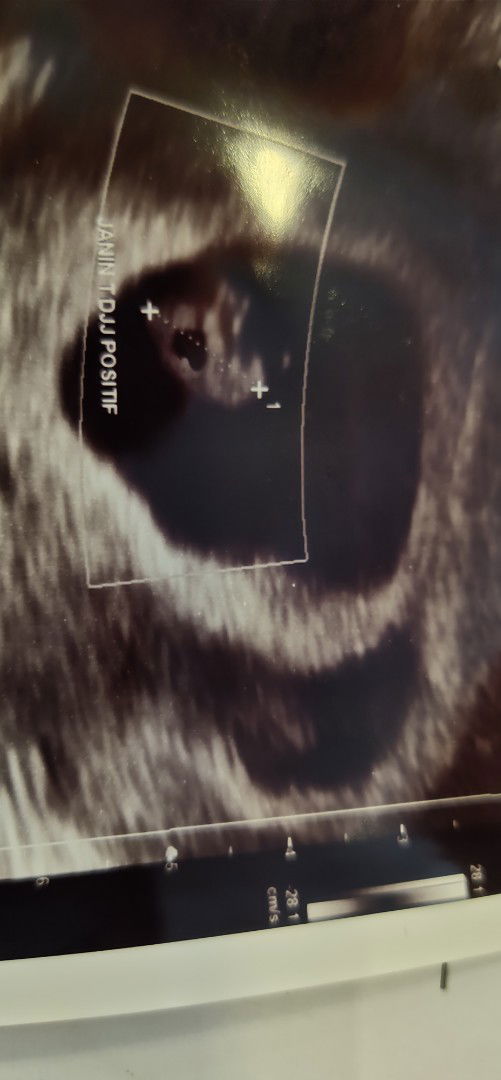

pendarahan subkrionik

Assalamualaikum, bunda2 mau sharing nih, ini kehamilan pertama setelah 4,5 thun menanti, lalu ini hsil USG minggu kmarin pas 7 week, alhamdulillah janin sdah ada denyut jantungnya, tp itu disebelah kanan kantung hamil kayak ada kantong lagi yg warnanya item, kata dokternya sih sinyal kalau ada pendarahan di rahim, lalu saya di resepkan duphaston sbg penguat kandungan, dan disarankan banyak istirahat Tp Alhamdulillah selama ini gejala hamil sperti mual, muntah gak ada bun, sampai flek2 juga ga ada, Semoga bisa sehat2 sampai lahiran yah bun, adakah bunda2 disini yg pernah ngalamin???